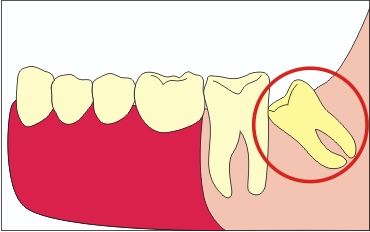

A mediális dőlése a Nyolcak Csoportja

Ez a rendelkezés tilt provokálja a fogszuvasodás kialakulásának, mint magától bölcsességfog, és a fogat állt mellette. Ha a lejtő erős, akkor a gyökér a hetedik foga is oldódni kezdenek, ami az ő eltávolítását. Ezen túlmenően, a csírázó az ilyen szögben, a fogat is elmozdulhatnak az egész sorozat, ami azt eredményezi, annak deformációját.